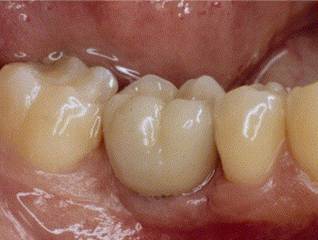

PROSTHESIS